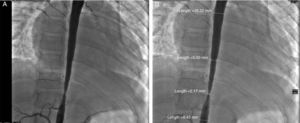

Glucocorticoids and methotrexate were initiated. Cardiac catheterization was performed due to the presence of more than 3 sites of stenosis. We documented diastolic dysfunction, mild mitral regurgitation; severe stenosis of the thoracoabdominal aorta with a gradient of 50mmHg and nonsevere renal artery stenosis (10mmHg gradient) (Fig. 2A and B). Angioplasty was performed in which two stents were placed in the stenotic area, with a postsurgical gradient of 0 (Fig. 3A and B). She is currently asymptomatic with no residual gradient. She no longer receives glucocorticoids but is receiving methotrexate, folic acid, vitamins A, C and D, aspirin, furosemide, spironolactone, and captopril.